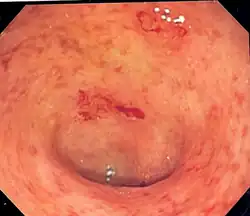

Ulcerózní kolitida

Ulcerózní kolitida (idiopatická proktokolitida) je chronické onemocnění střevní sliznice. Je to onemocnění, které začíná obvykle postižením konečníku a omezuje se na tlusté střevo, zřídkakdy může být zánětem poškozena i konečná část tenkého střeva (terminální ileum). Ulcerózní kolitida poškozuje sliznici a působí zánětlivé změny a vředy na jejím povrchu. Onemocnění probíhá chronicky, často se střídají klidná bezpříznaková období s fázemi aktivace nemoci.

Zánětlivé změny mohou způsobit bolesti, častější vyprazdňování a průjem. V místech, kde je sliznice zánětem narušena, se tvoří vředy, které mohou krvácet a vylučovat hlen a hnis. Mezi hlavní příznaky ulcerózní kolitidy patří:

Střevní příznaky

Střevní příznaky se odlišují podle stupně a rozsahu poškození střeva. Při ulcerózní kolitidě je prakticky vždy postižen konečník.

Dráždění této oblasti probíhajícím zánětlivým onemocněním se projevuje nutkavým pocitem na stolici, přičemž při defekaci se vyprázdní pouze malé množství stolice s hlenem nebo čerstvou krví.

Vyprazdňování je většinou spojeno s bolestí. Nemusí se ani jednat o průjem, tedy řídkou stolici, typická je ale právě přítomnost krve. U těžkého stupně choroby může být takových stolic i více než 15 za den.

Endoskopické metody

Kolonoskopie je vyšetření, které umožňuje lékaři prohlédnout si prostřednictvím sondy s kamerou a s optickými vlákny vnitřek střeva. Endoskopický přístroj je zaveden konečníkem a pokračuje dále do tlustého střeva.